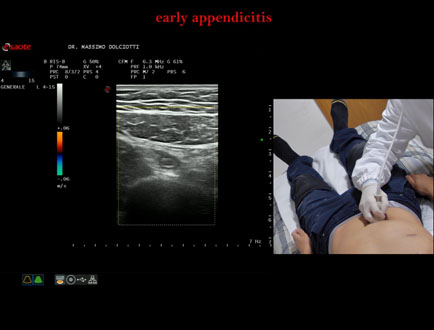

Data inserimento: 13/11/2025

Ecografia del: 10/11/2025

Strumento: Esaote MyLab Eight

Sonda: Lineare Multifrequenza 4-15 MHz

Età Paziente: M 26 anni

Motivazione dell'esame: da 2 settimane dolori addominali.

Commento all'esame: le immagini ed il video documentano il verme appendicolare, dello spessore trasversale di 9,1 mm e diametro longitudinale di 8,8 mm, con scarsi segnali di vascolarizzazione, da ricondurre ad appendicite in fase iniziale.

Conclusioni: appendicite in fase iniziale (early appendicitis).

Presentazione: Dr. Massimo Dolciotti - Ancona